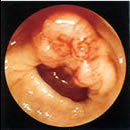

癌の内視鏡写真 |

肛門から内視鏡(ファイバースコープ)を挿入して、腸管の様子を直接観察する検査です。

この検査法では、わずか数ミリのポリープであっても見落としなく発見できます。